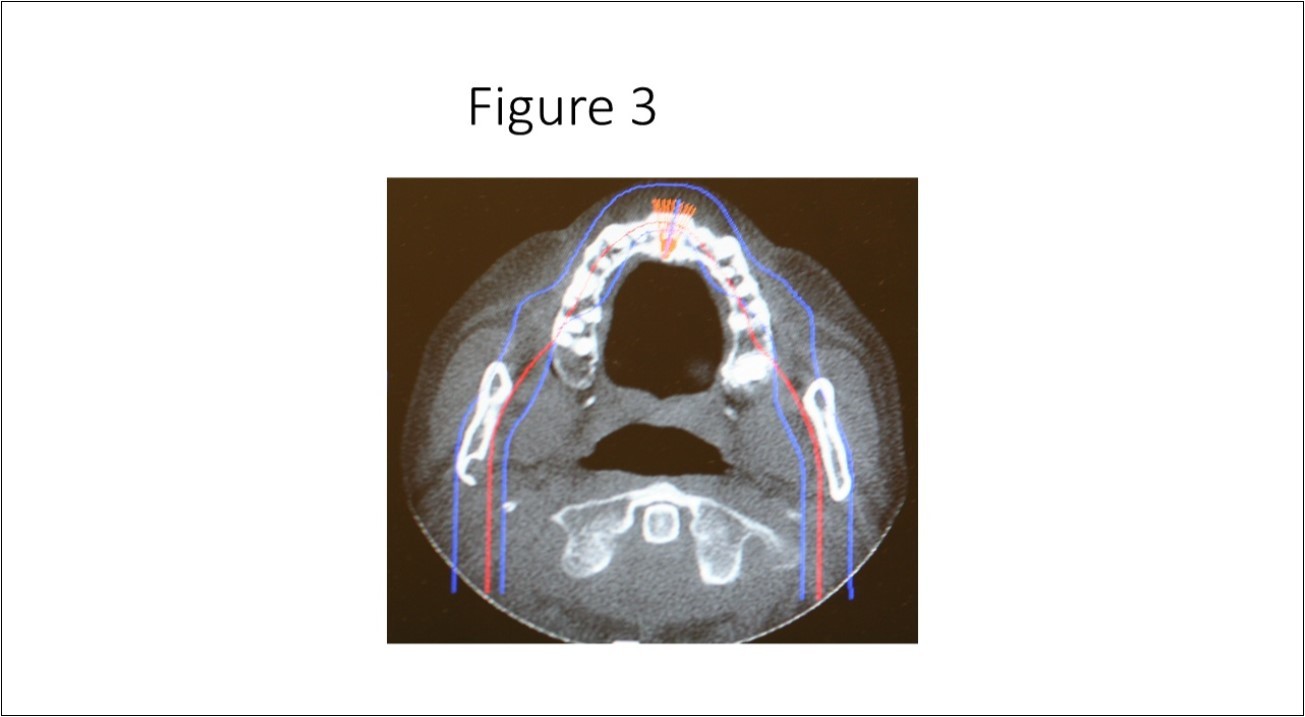

Maxillofacial examination was unremarkable. No facial swelling, masses or asymmetry was observed. The TMJ examination was normal. No pain or tenderness to digital palpation was observed in the right preauricular region. Oral examination of the patient was unremarkable. No trismus was observed as the maximal interincisive opening was greater than 40.0mm. No anterior or posterior open bite was observed. Imagining studies to rule-out intraosseous neoplastic lesions and arrive at a definitive diagnosis consisted of a panoramic radiograph and cone beam CT scan (120 kVp, 5 mA, 7.4 sec). Panoramic radiograph revealed a unilocular, well-circumscribed radiolucency in the right subcondyalar region of the mandible that was close to the posterior border of the condylar neck (Figure 2). Cone beam CT scan (i-CAT FLX, Imaging Sciences, Hatfield, PA) imaging revealed a well-defined unilocular, elliptical shaped radiolucent lesion on the medial surface of the right subcondylar neck of the mandible (Figure 3, Figure 4, Figure 5). The elliptical shaped unilocular lesion involved almost the entire horizontal dimension of the subcondylar neck (Figure 4). Figure 5 shows the three-dimensional CT scan reconstruction (i-CAT FLX, Imaging Sciences, Hatfield, PA) of the medial defect in the subcondylar region of the mandible. Based on knowledge of clinical head and neck anatomy and imaging studies, no treatment was indicated as the diagnosis was consistent with a variant of a Stafne bone cavity of the right subcondylar neck near the parotid gland and not a pathological condition. The patient was informed about the risk of condylar neck fracture due to the critical size of the SBC.

Figure 3.Axial cone beam CT scan showing osseous bone defect with herniation of soft tissue in the medial cortex of the right subcondylar neck of the mandible.

Axial cone beam CT scan showing osseous bone defect with herniation of soft tissue in the medial cortex of the right subcondylar neck of the mandible.

Stafne bone cavity located in the subcondylar region of the mandible is considered a rare variant of the well-described SBC in the mandibular posterior mandible first reported by Stafne in 1942. There is a paucity of published case reports of SBC identified in the subcondylar or ascending ramus of the mandible in the English world medical and dental literature.9,19In a study by Sisman et al 3using computed tomography they concluded that the SBC is due to the presence of aberrant submandibular gland tissue within the osseous defect on the medial surface of the mandible. As it is hypothesized that the submandibular gland tissue is entrapped that leads to an osseous concavity on the medial surface of the mandible, it is also plausible that the parenchymal tissues of the parotid gland can also become entrapped in the developing mandible that leads to a similar osseous concavity (Figure 3) in the subcondylar region of the mandible.20